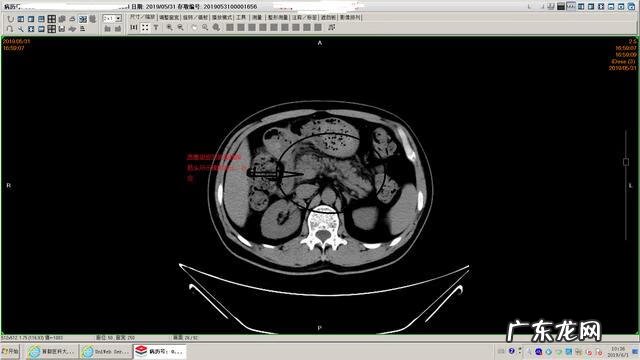

可疑胆总管结石

胰腺模糊渗出 , 坏死不明显

淀粉酶升高 , 胆红素正常

胰腺间隙模糊

胃内有残余食物

【胰腺炎吃什么好得快 胰腺炎吃什么药效果最好】肠道积存大量粪便